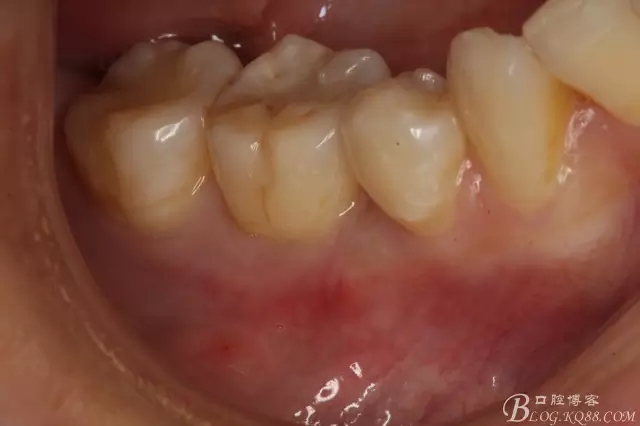

圖3.口內(nèi)頰側(cè)像,46、44鄰接正常,兩個牙頰側(cè)牙齦乳頭正常。45牙根完全埋伏于齦下。